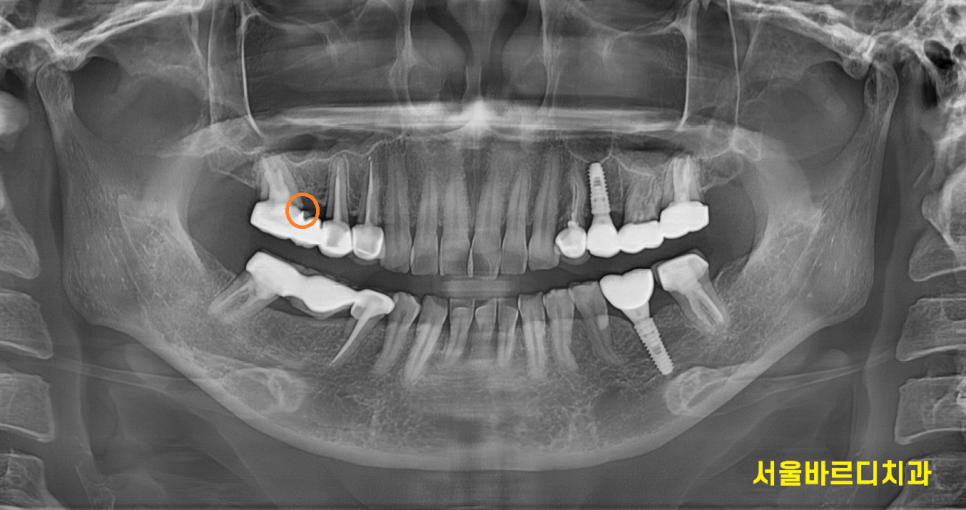

230814

맨 처음 저희 병원 오셨을 때부터

뿌리쪽 충치도 보이고

치아가 안좋지만 뽑기에는 아까우니

쓸 때까지 쓰라고 말씀드렸던 부분입니다.

겉으로 눈으로 보기에는 멀쩡해보이는데

x-ray를 찍으면 다 보입니다~